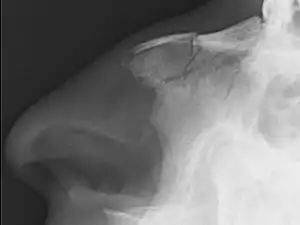

Nasal fractures are usually identified visually and through physical examination.[1] Medical imaging is generally not recommended.[1][2] A priority is to distinguish simple fractures limited to the nasal bones (Type 1) from fractures that also involve other facial bones and/or the nasal septum (Types 2 and 3). In simple Type 1 fractures X-Rays supply surprisingly little information beyond clinical examination. However, diagnosis may be confirmed with X-rays or CT scans, and these are required if other facial injuries are suspected.[2]

Nasal bone fracture

Bilateral nasal fracture as seen on CT scan